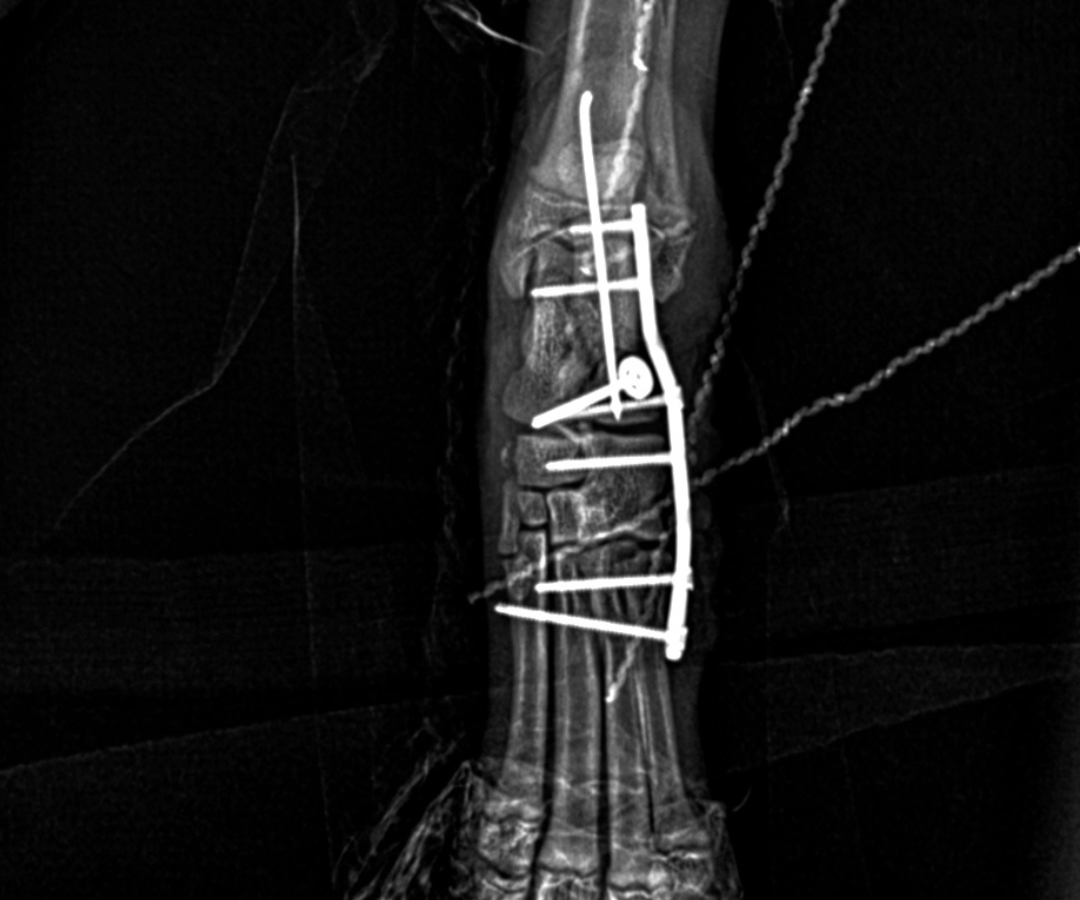

The first priority was bringing the broken heel bone back into alignment. A fine pin (1.1 mm intramedullary pin) was passed retrogradely through the calcaneal fragments, essentially acting as an internal scaffolding rod, holding the pieces together while the more complex reconstruction took place around them.

With the heel bone provisionally stable, the team turned their attention to Ralphie’s dislocated joints. Because several of the small tarsal joints had been thrown completely out of position, they needed to be temporarily bridged and held still to allow the disrupted ligaments time to heal. A slim, precision locking plate (a 1.5 mm 8-hole RL Leilox plate) was secured along the outer side of the ankle region. This specialised implant bridged across the small bones of the hock joint, running from the metatarsal (foot) bones, through the central tarsal and fourth tarsal bones in the ankle, and anchoring into the calcaneus (heel bone). This provided stability across the affected area.

Locking screws anchored at multiple points meant that the load was distributed across the repair rather than concentrating stress at any single fixation point, which is particularly important in a puppy's developing bone. An additional cortical screw fitted with a small washer was inserted through the lower fragment of the calcaneus (heel bone) and into the talus (the bone sitting directly above the heel) to further strengthen and stabilise the overall repair.

One of the more technically demanding aspects of Ralphie's case involved a small, flake-like bone fragment at the centroquartal joint - the junction between the central and fourth tarsal bones. Here, the long plantar ligament had partially torn away. Because the fragment was too small and delicate to hold a conventional screw or pin, stabilising it with standard hardware was not an option.

Instead, the surgical team reattached the ligament by passing sutures through small tunnels carefully drilled into the main body of the heel bone. This tunnel technique restores the critical load-bearing and stabilising function of the plantar ligament while avoiding the risk of fragmenting tissue that simply cannot support metallic implants.

Post-operative X-rays confirmed that the fractured bones had been successfully realigned and that all implants were correctly positioned.